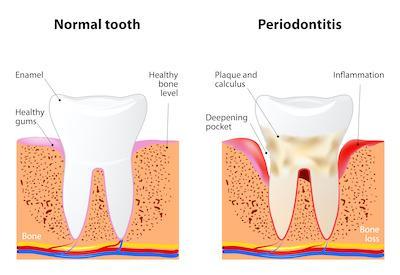

Periodontal disease is a serious infection of the tissues surrounding your teeth. These gum infections, when left untreated, may lead to tooth loss and even full-body health concerns.

Unfortunately, periodontal disease does not always present with noticeable symptoms, especially early in the condition. Because of this, patients often don’t visit the dentist until gum disease moves out of the treatable gingivitis stage.

- A longish appearance to your teeth as gums recede

- Pocketing between your teeth and your gums as damaged tissues pull away from teeth

When the periodontal infection is allowed to progress to advanced stages (periodontitis), it loosens stabilizing tissues around the teeth, opening up small pockets where bacteria thrive. Noninvasive laser dentistry gently excises diseased dental material from these areas faster than traditional methods.